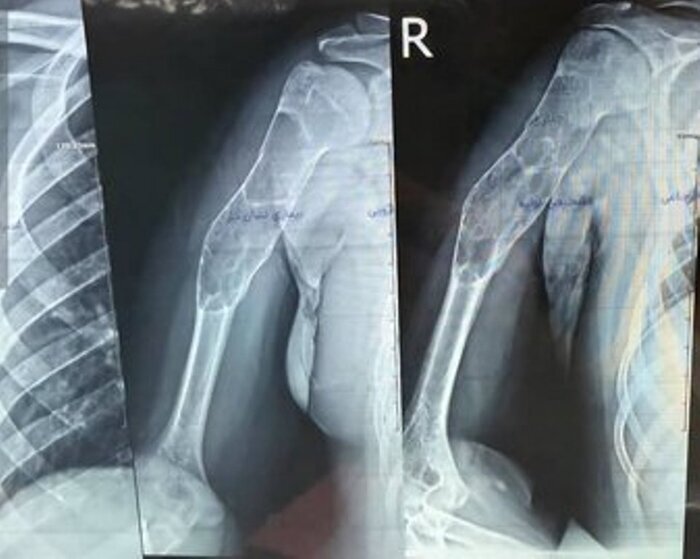

دکتر شهریار خوشبخت، جراح و متخصص ارتوپدی هم درباره این عمل جراحی گفت: با توجه به وجود توده کیستیک وسیع در بازوی بیمار، تیم جراحی توانست به مدت سه ساعت پس از عملیات پلاکگذاری، توده وسیع را تخلیه و استخوان مصنوعی را جایگزین کند.

وی افزود: چنین اعمال پیچیدهای به طور معمول توسط فوق تخصصهای جراحی دست در مراکز استانها انجام میشود و خوشبختانه توانستیم برای اولین بار در شمال استان اردبیل در بیمارستان امام (ره) پارسآباد این عمل را با موفقیت انجام دهیم و اکنون بیمار با حال عمومی خوب بستری است و پس از چند روز مرخص خواهد شد.